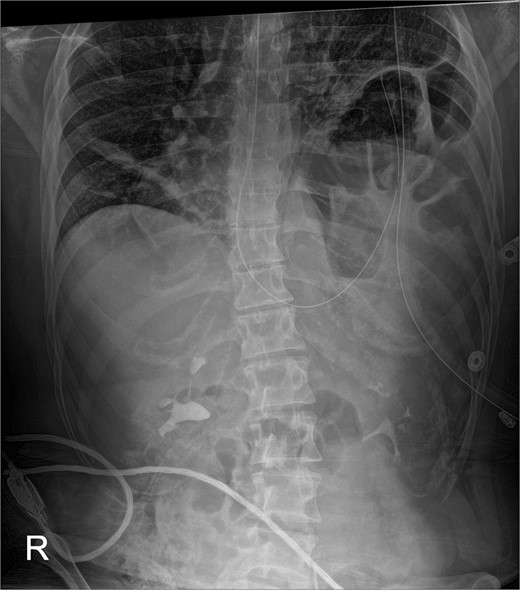

This is a case of a 26-year-old male patient who presented with symptoms of dyspnea on exertion, left chest pressure, and constipation for 7 years. He was a never smoker with no history of trauma, nor prior neck and chest surgeries. Baseline pulmonary functions tests revealed FEV1 of 71% predicted and DLCO of 77% predicted. Work-up included a computed tomography (CT) of the chest which revealed marked left hemidiaphragm elevation with compression atelectasis of the left lower lobe (Fig. 1). A fluoroscopic sniff test showed paradoxical movement of the left hemidiaphragm consistent with diaphragmatic paralysis. Interestingly, abdominal imaging obtained 14 months before surgery showed a displaced stomach but without volvulus (Fig. 2). Due to the impact on the patient’s quality of life, he was offered surgical treatment with a robotic-assisted left thoracoscopic plication of the diaphragm. This was done using a three-arm technique using the Da Vinci Xi surgical system (Intuitive Surgical, Sunnyvale, CA) with an additional assistant port. Plication was performed by placing multiple horizontal mattresses sutures reinforced with pledgets in an anterior–posterior orientation, and systematically working medial to lateral. A postoperative chest X-ray showed a satisfactory result (Fig. 3).

Immediate post-operative film demonstrates intact repair, and well-positioned chest-tube.

The early postoperative course was unremarkable. The patient reported feeling mild bloating, but was discharged on postoperative Day 1 after removal of a chest tube (Fig. 4). A few hours after discharge from the hospital, he developed dysphagia, progressive abdominal pain, distension, and dyspnea that prompted a return to the hospital. Physical examination revealed tachycardia (132 bpm), mild hypoxia requiring supplemental O2 at 2 L/min via nasal canula, and abdominal distension. Laboratory studies showed WBC of 12 600 cells/μL. A CT scan of the abdomen and pelvis revealed a large, acute organo-axial gastric volvulus without evidence of ischemia, and an intact left hemidiaphragm plication at a similar height to the right hemidiaphragm (Fig. 5). A nasogastric tube was placed with immediate drainage of 1 L of dark bilious fluid with immediate relief of the patient’s symptoms. However, a subsequent film revealed the nasogastric tube projecting toward the upper left chest with presence of colonic haustra (Fig. 6), consistent with acute hemidiaphragm rupture.

Following chest-tube removal, a film was taken, revealing even hemi-diaphragms, which was notably higher than immediate post-operatively, but within normal limits.

Confirmatory abdominal film for nasogastric tube placement demonstrating acute elevation in the left hemidiaphragm, 90-min after the CT, identifying the gastric volvulus.